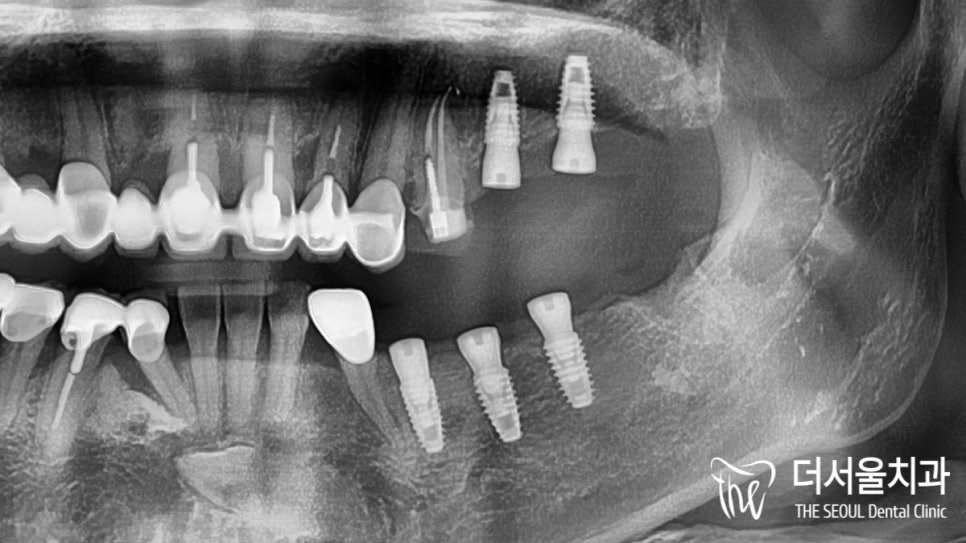

분석된 내용을 바탕으로

정해진 위치에 심어드렸습니다.

염증이 꽤 깊은 곳까지 퍼져 있어서

초기고정력을 얻을 수 있을까 걱정이 되었는데요.

다행히 별다른 문제 없이

제위치에 심어진 것을 확인할 수 있었습니다.

골융합 및 회복 정도를 확인한 뒤

완성된 보철을 올려드리며

네비게이션 임플란트 의

마무리를 도와드렸습니다.